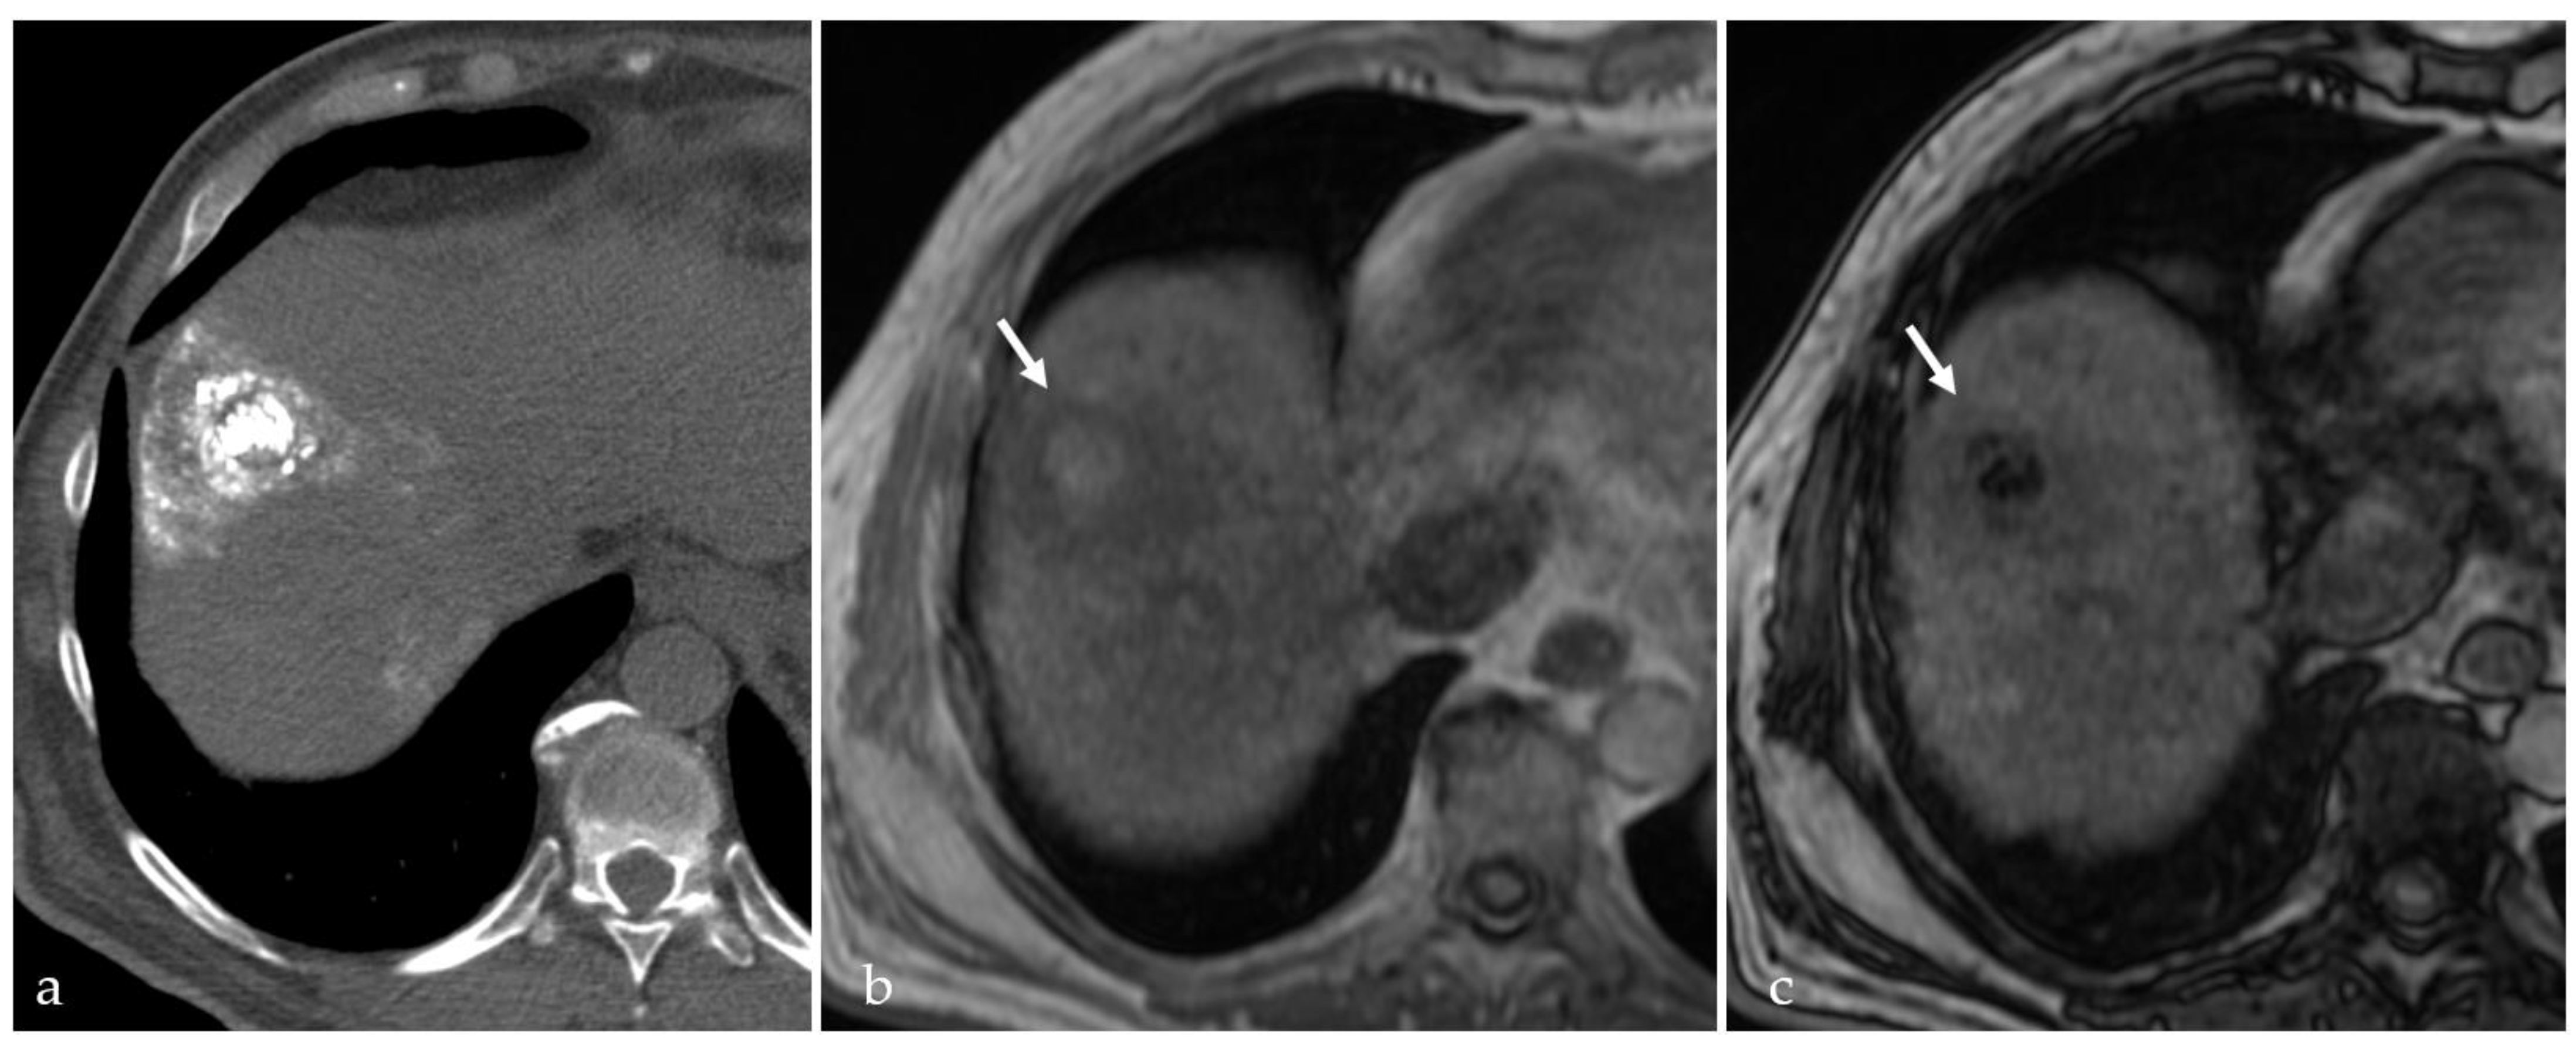

3.2. Expected Post-Treatment Imaging Features in the Absence of Viable Tumor Tissue

3.4. TACE-Associated Necrosis

3.5. Post-Treatment Imaging Features of Tumor Viability